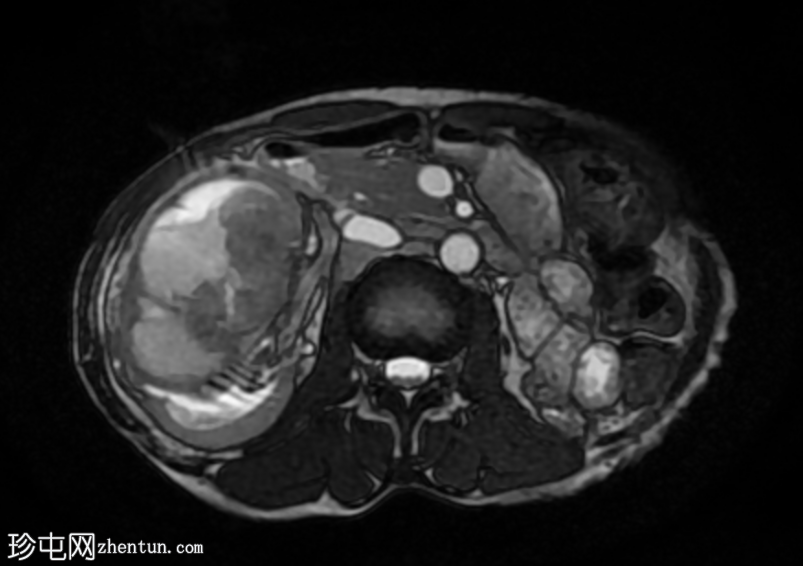

轴位

T2加权像

再次观察到上述肾前部外生性病变,其实性成分在T1加权像上呈等高信号,在T2加权像上呈低信号,伴有碎片扩散受限和低ADC值(化脓性物质)。囊性成分内部可见液-碎片/脓液界面。可见内部低信号结石。可见肾周模糊影。该病变压迫并可能侵犯右肾盂,导致中度肾积水。

病灶不规则的低信号,以及液-液界面伴有碎屑(可能为化脓性物质)扩散受限和肾周模糊,再次高度提示炎症性病变(黄色肉芽肿性肾盂肾炎,XGP),而非可能性较小的肿瘤。

左肾萎缩,体积较小,内含多发低信号结石。